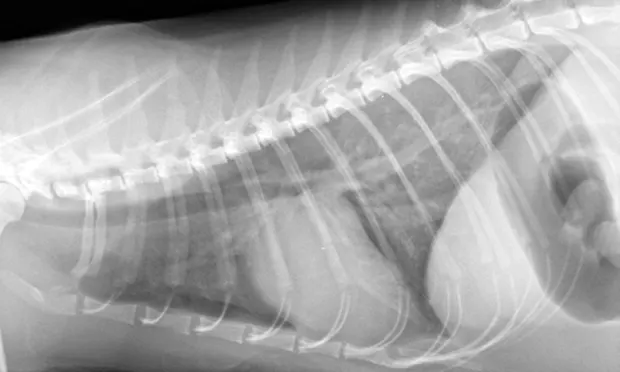

Thoracic radiography (Figure 2) revealed cardiomegaly (vertebral heart score of 8 [range, 7.2–7.8]) characterized by left atrial and ventricular enlargement, distended pulmonary veins, and a pulmonary interstitial pattern. The location of the pulmonary edema was more severe in the left lung lobe. Feline pulmonary edema may not follow the classic caudodorsal and perihilar distribution pattern noted in canine patients.

Figure 2 Right lateral (A) and dorsoventral (B) thoracic radiographs showing cardiomegaly, pulmonary venous distention (white arrows), and pulmonary interstitial densities (black arrows)